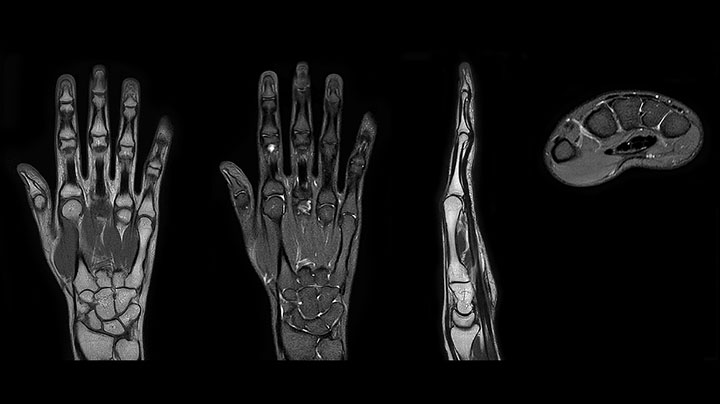

MRI of hand and wrist with large FOV

Prodiva imaging of the hand covers the fingertips and includes the full wrist as well. The dS MSK M coil is easy to use.

“The quality of the contrast-free MR angiography keeps impressing us,” says Mrs. Schiffer. “In addition to not having to inject contrast agent, these images are amazing, for instance of the carotids. Also our exams of shoulders and hands are really exceptional. Images of the hands, for example, cover the fingertips and include the full wrist as well, all with high signal-to-noise ratio.”